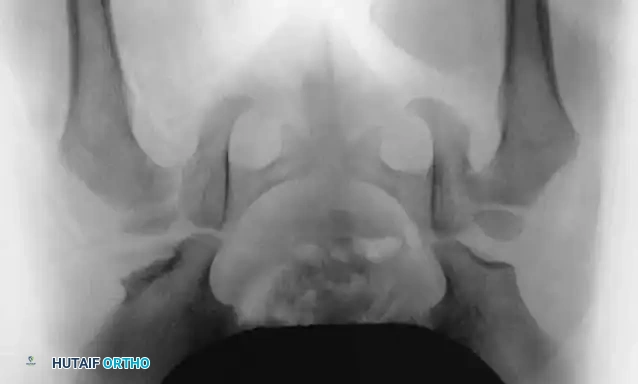

In newborns, radiographs are notoriously unreliable due to the unossified cartilaginous nature of the femoral head and acetabulum. Diagnosis relies heavily on dynamic clinical testing and ultrasonography.

Radiography: Becomes reliable after 4 to 6 months as the ossific nucleus of the femoral head appears. Key radiographic parameters include:

* Hilgenreiner's Line: A horizontal line through the triradiate cartilages.

* Perkins' Line: A vertical line dropped from the lateral margin of the acetabulum, perpendicular to Hilgenreiner's line.

* Shenton's Line: A continuous arc drawn from the medial border of the femoral neck to the superior border of the obturator foramen. Disruption indicates proximal migration.

* Acetabular Index: The angle between Hilgenreiner's line and a line drawn from the triradiate cartilage to the lateral edge of the acetabulum. Normal is <30 degrees in newborns; >35 degrees is highly suspicious for dysplasia.

Radiographic evaluation: Normal hip anatomy (left) versus Dysplastic hip anatomy (right) demonstrating disruption of Shenton's line and an increased acetabular index.